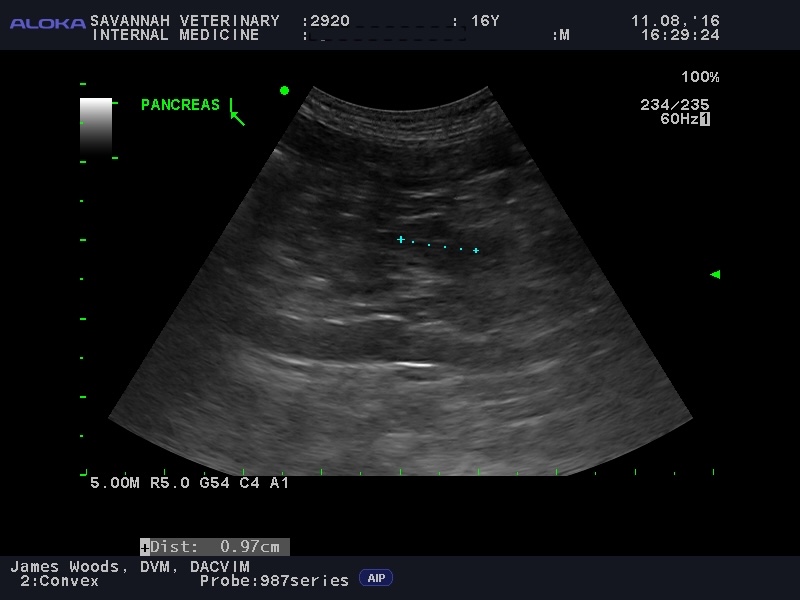

Visualizing The Pancreas: For the diagnosis of feline pancreatitis, an abdominal ultrasound is an important diagnostic tool. While X-rays are typically not very useful, ultrasound provides a non-invasive way to visualize the pancreas. The accuracy of ultrasound is highly dependent on the skill of the operator, as the pancreas can be difficult to locate and assess in cats. At Savannah Veterinary Internal Medicine, our team performs detailed ultrasounds to help identify pancreatitis, even in subtle cases. Even more so than the fPLI test, ultrasound may be normal in cats with mild, or chronic pancreatitis.

To illustrate this diagnostic challenge, the appearance of the pancreas on ultrasound varies significantly between different forms of the disease:

Acute vs. Chronic Feline Pancreatitis Ultrasound Images:

Recognize the varied imaging features of the inflamed feline pancreas, where acute and chronic forms present with distinct ultrasonographic changes.